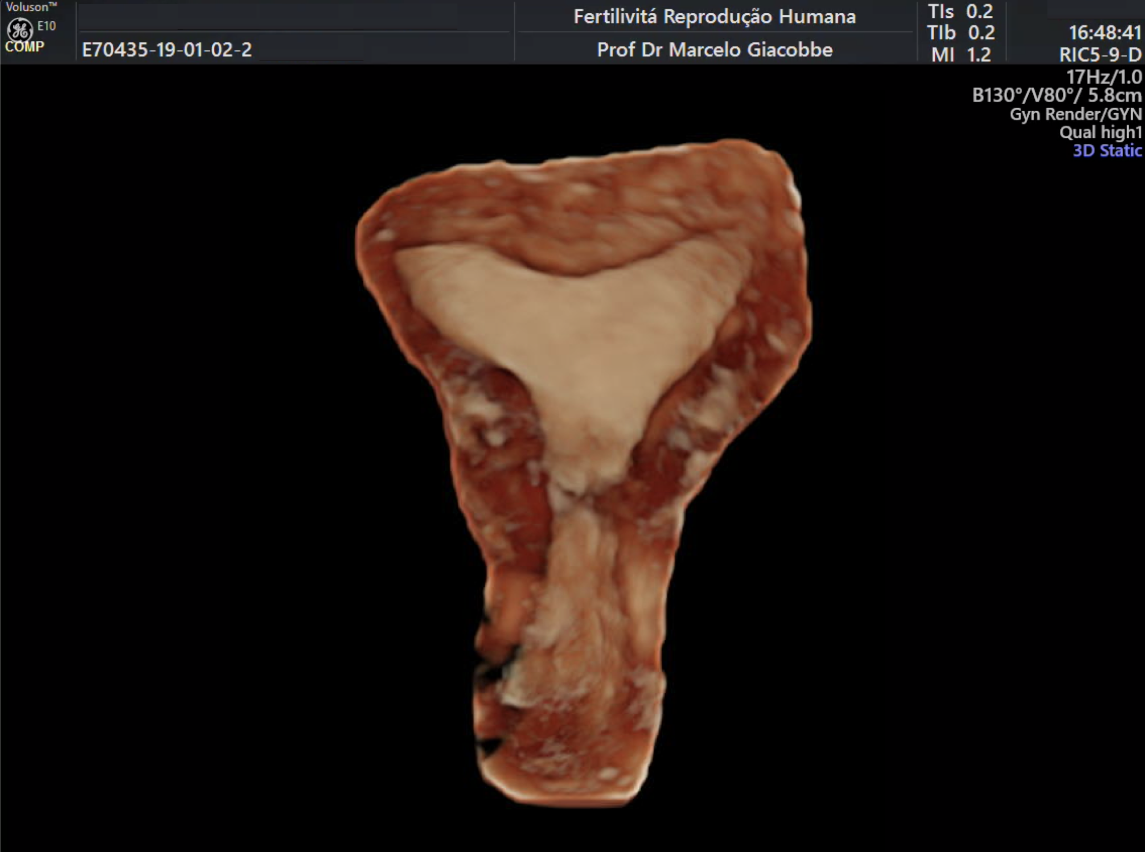

(A)

(B)

(C)

Imagem de ultrassom convencional mostrando pólipo (A), pólipo ao Doppler em cores (B) e ultrassom tridimensional VCI realçando o pólipo no endométrio (C).